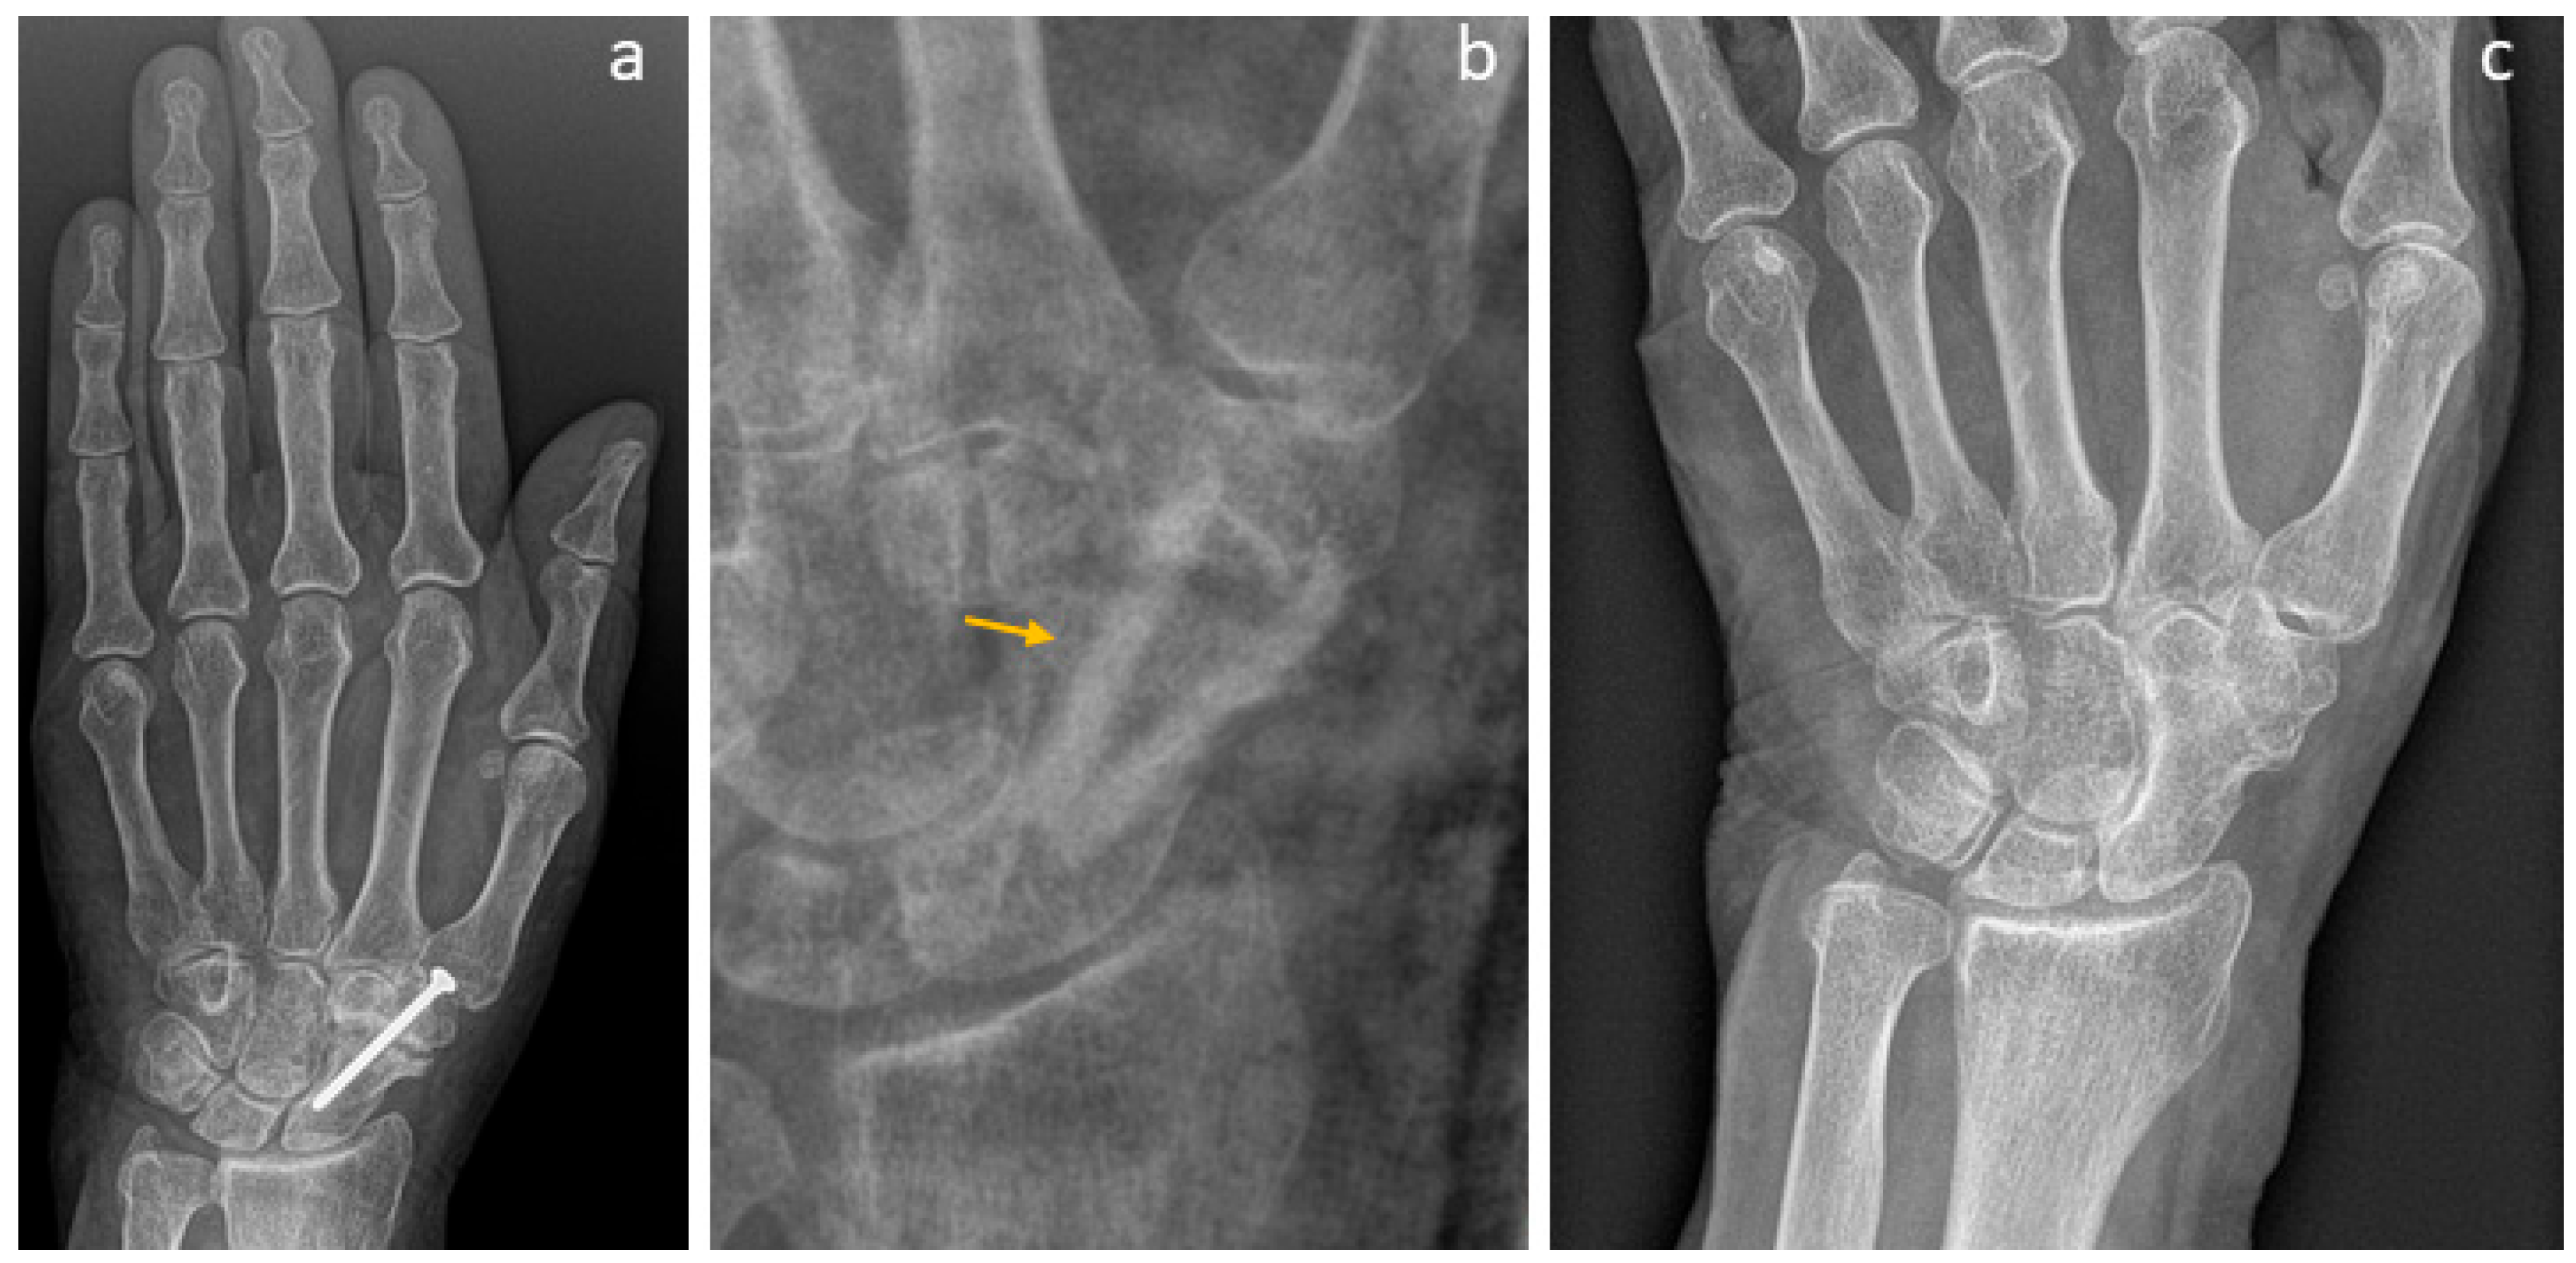

3.4. Selected Case Descriptions